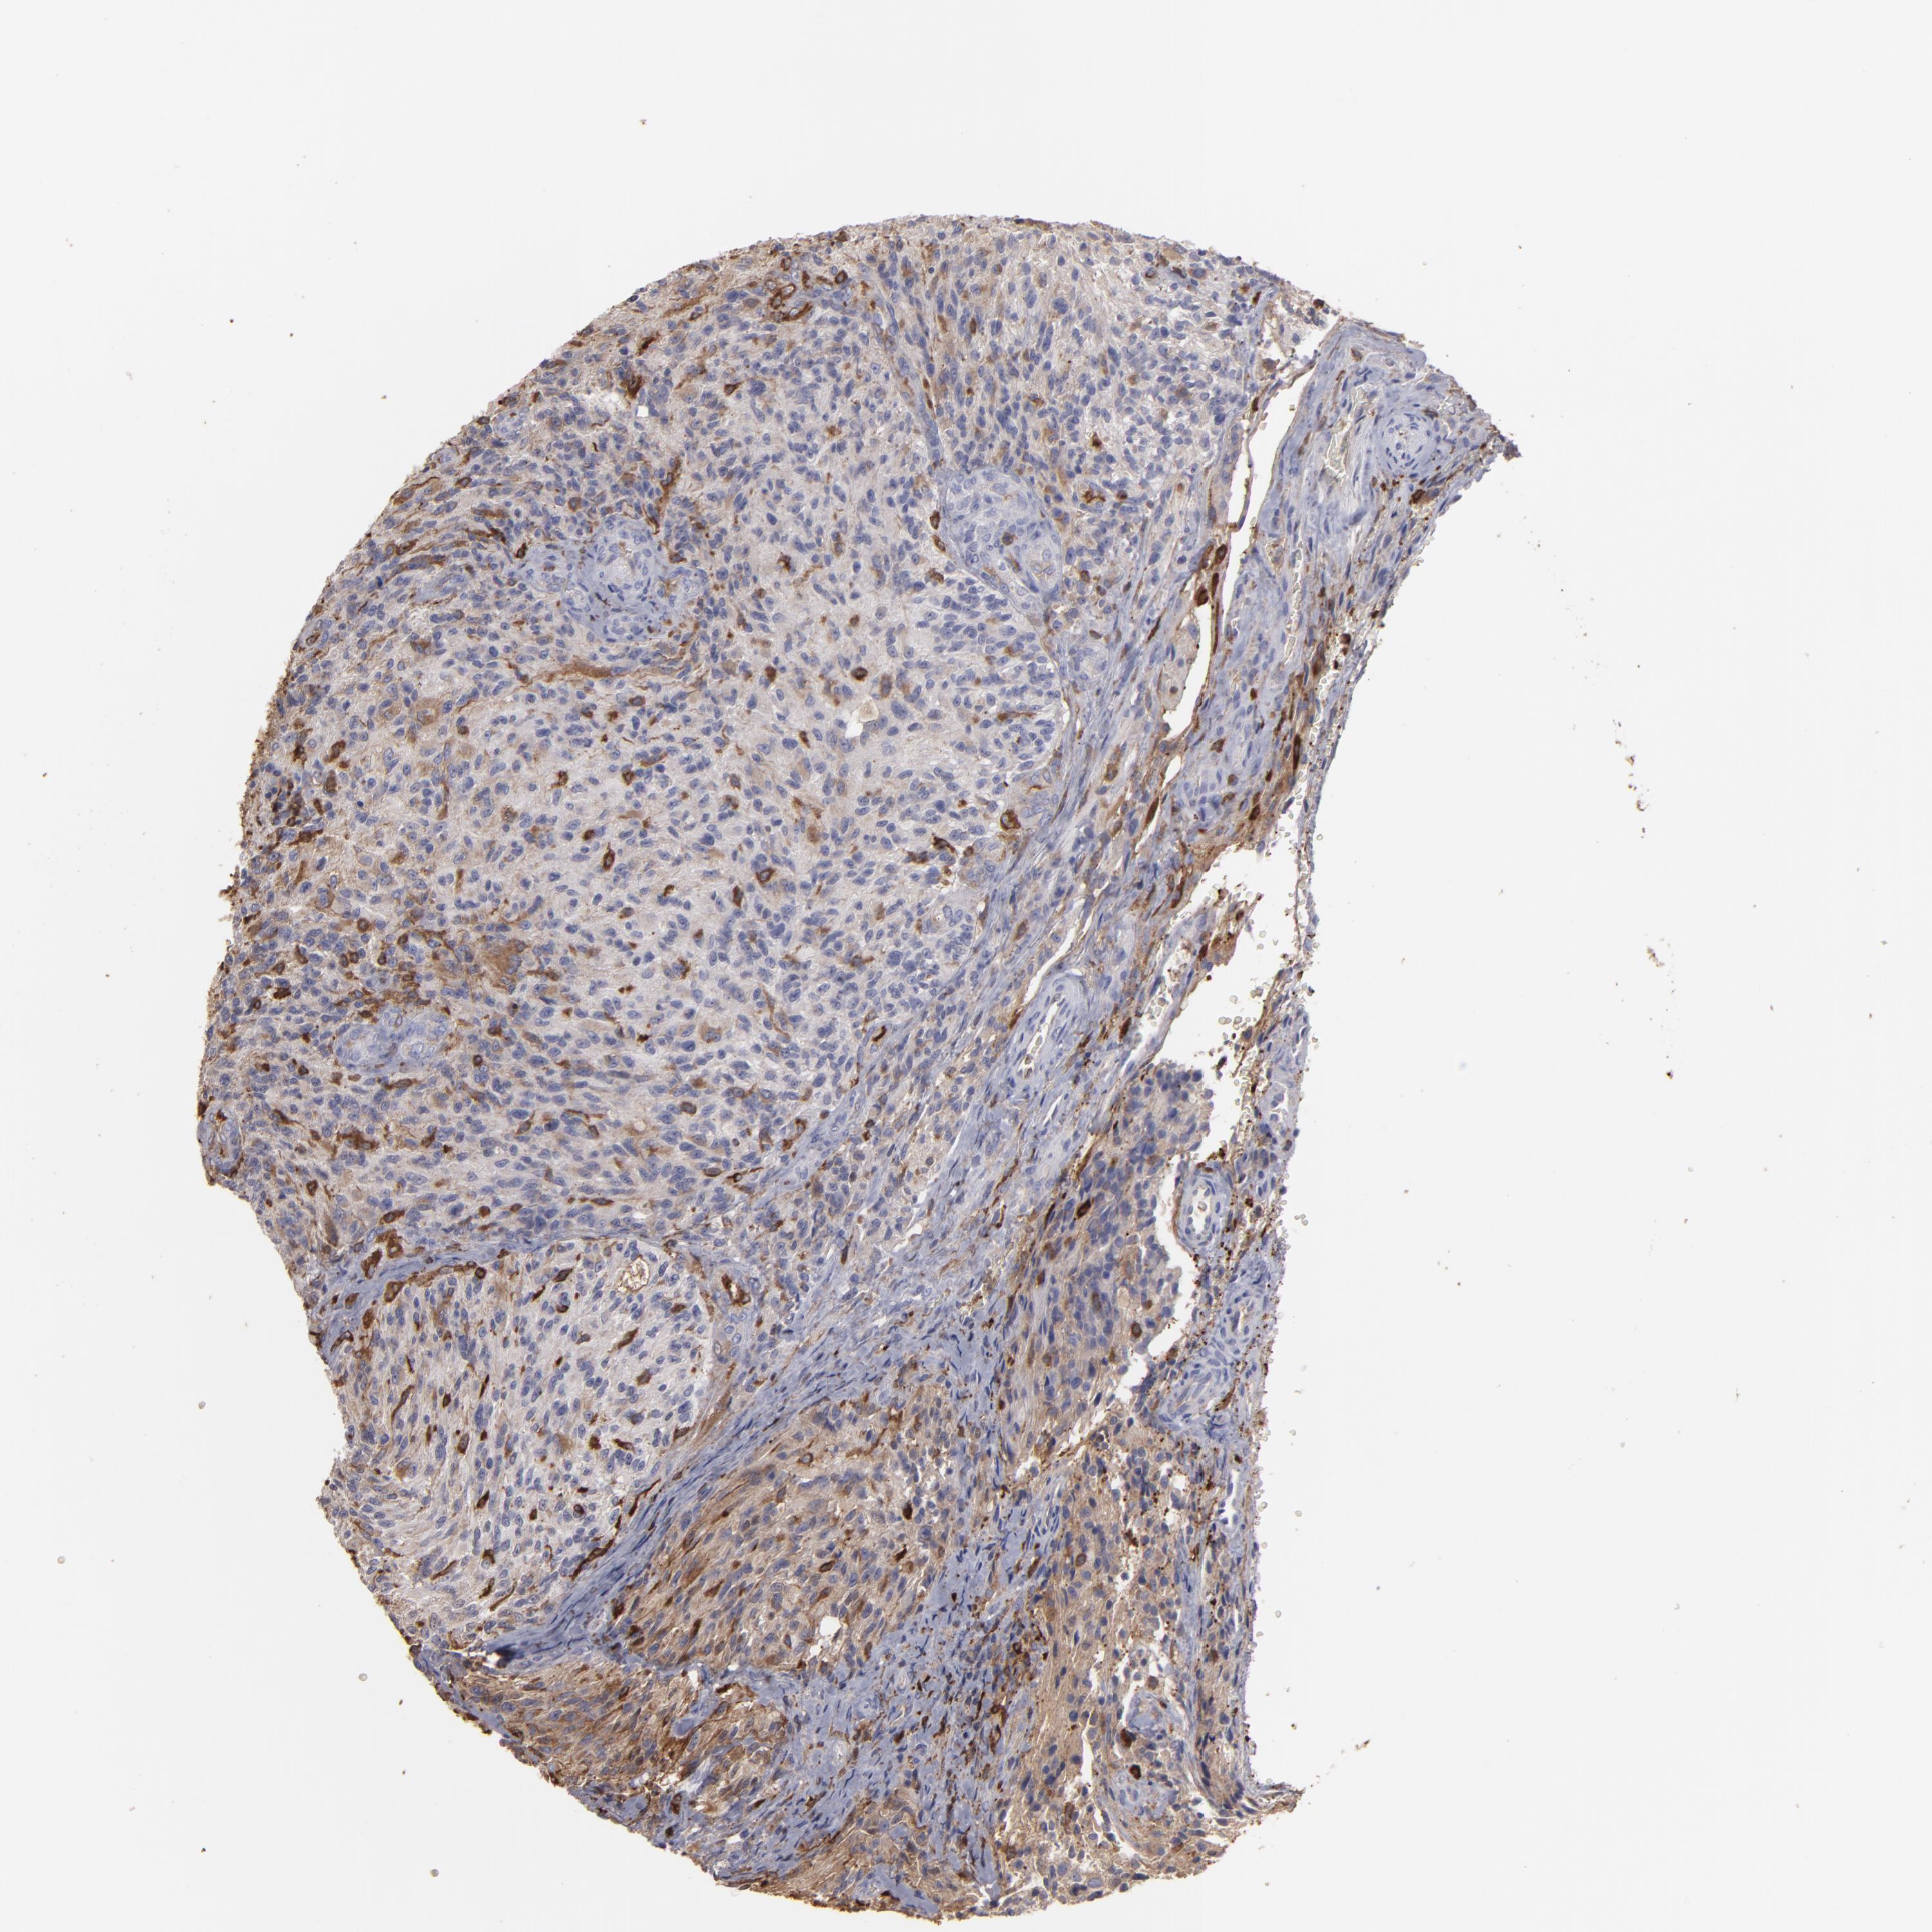

GLIOMA - Protein expressioni

A mouse-over function shows sample information and annotation data. Click on an image to view it in a full screen mode. Samples can be filtered based on level of antibody staining by selecting one or several of the following categories: high, medium, low and not detected. The assay and annotation is described here.

Note that samples used for immunohistochemistry by the Human Protein Atlas do not correspond to samples in the TCGA dataset.

Antibody stainingi

Antibody staining in the annotated cell types in the current human tissue is reported as not detected, low, medium, or high, based on conventional immunohistochemistry profiling in selected tissues. This score is based on the combination of the staining intensity and fraction of stained cells.

Each image is clickable and will lead to virtual microscopy that enables deeper exploration of all samples and also displays staining intensity scores, fraction scores and subcellular localization as well as patient and tissue information for each sample.

Antibody HPA001536

Antibody CAB035996

Staining

High

Medium

Low

Not detected

Intensity

Strong

Moderate

Weak

Negative

Quantity

>75%

75%-25%

<25%

None

Location

Nuclear

Cytoplasmic/membranous

Cytoplasmic/membranous,nuclear

Glioma, malignant, High grade

Glioma, malignant, Low grade

Glioma, malignant, NOS

Glioblastoma, NOS